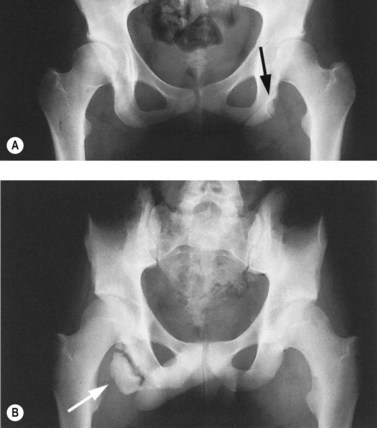

With osteitis pubis no instability of the pubic symphysis occurs, but there is tenderness over the area with rarefaction of the pubic bones and sometimes widening of the symphysis pubis apparent on x-ray. Erosion of the superior and inferior aspects of the symphysis may also occur (Fig. 8.13). The athlete often has a waddling gait, and may describe occasional crepitus. Severe (long-term) cases may progress to sclerosis and eventual narrowing of the symphysial joint space requiring wedge resection (Grace, Shives and Coventry, 1989). Bone marrow oedema may be visible on MRI scan.

image

Figure 8.13 Osteitis pubis. (A) Anterior and (B) posterior view showing bone fragment.

From Magee (2002) with permission.

Palpation may be used to differentiate true osteitis pubis from tendinitis of the gracilis or avulsion injury to the gracilis attachment. The gracilis muscle attaches to the inferior aspect of the symphysis and local palpation may reveal spot tenderness (Fig. 8.14). Both of these conditions give pain to resisted adduction as well as to local palpation. Importantly, osteitis pubis often gives pain to pelvic springing tests to the iliac crest whilst gracilis conditions do not. The condition may be graded as illustrated in Table 8.4.